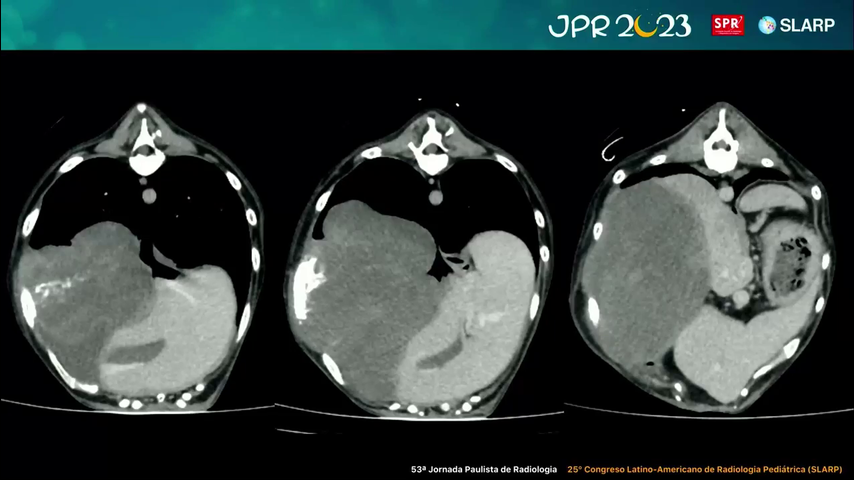

Caso de Tomografia